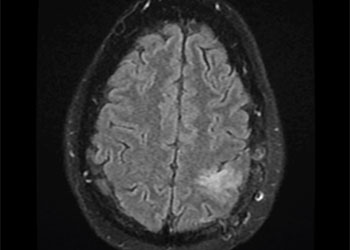

A teenage boy presented with 6 months of weight loss and difficulty swallowing. A contrast-enhancing mass in the brainstem and upper cervical cord was found which was suspicious of a symptomatic hemangioblastoma (Figure 1).

Symptoms from the slowly growing tumor stem from mass effect caused by the cystic component and the tumor. Contrast-enhanced brain MRI shows a hypervascular tumor. However, the exact location of the tumor in terms of intra- or extramedullary or intraand extramedullary can be difficult to determine on imaging and may only be clarified during surgery5.